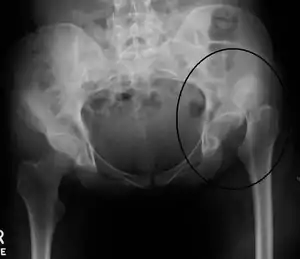

| گرافی دررفتگی ران سمت چپ | |